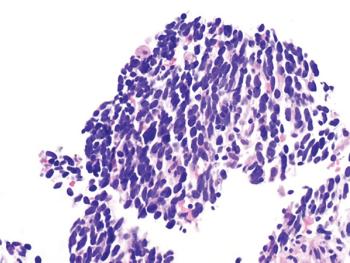

A study, published in Nature Cancer, demonstrates the quick and evolving revolutions of resistance mechanisms in small cell lung cancer.